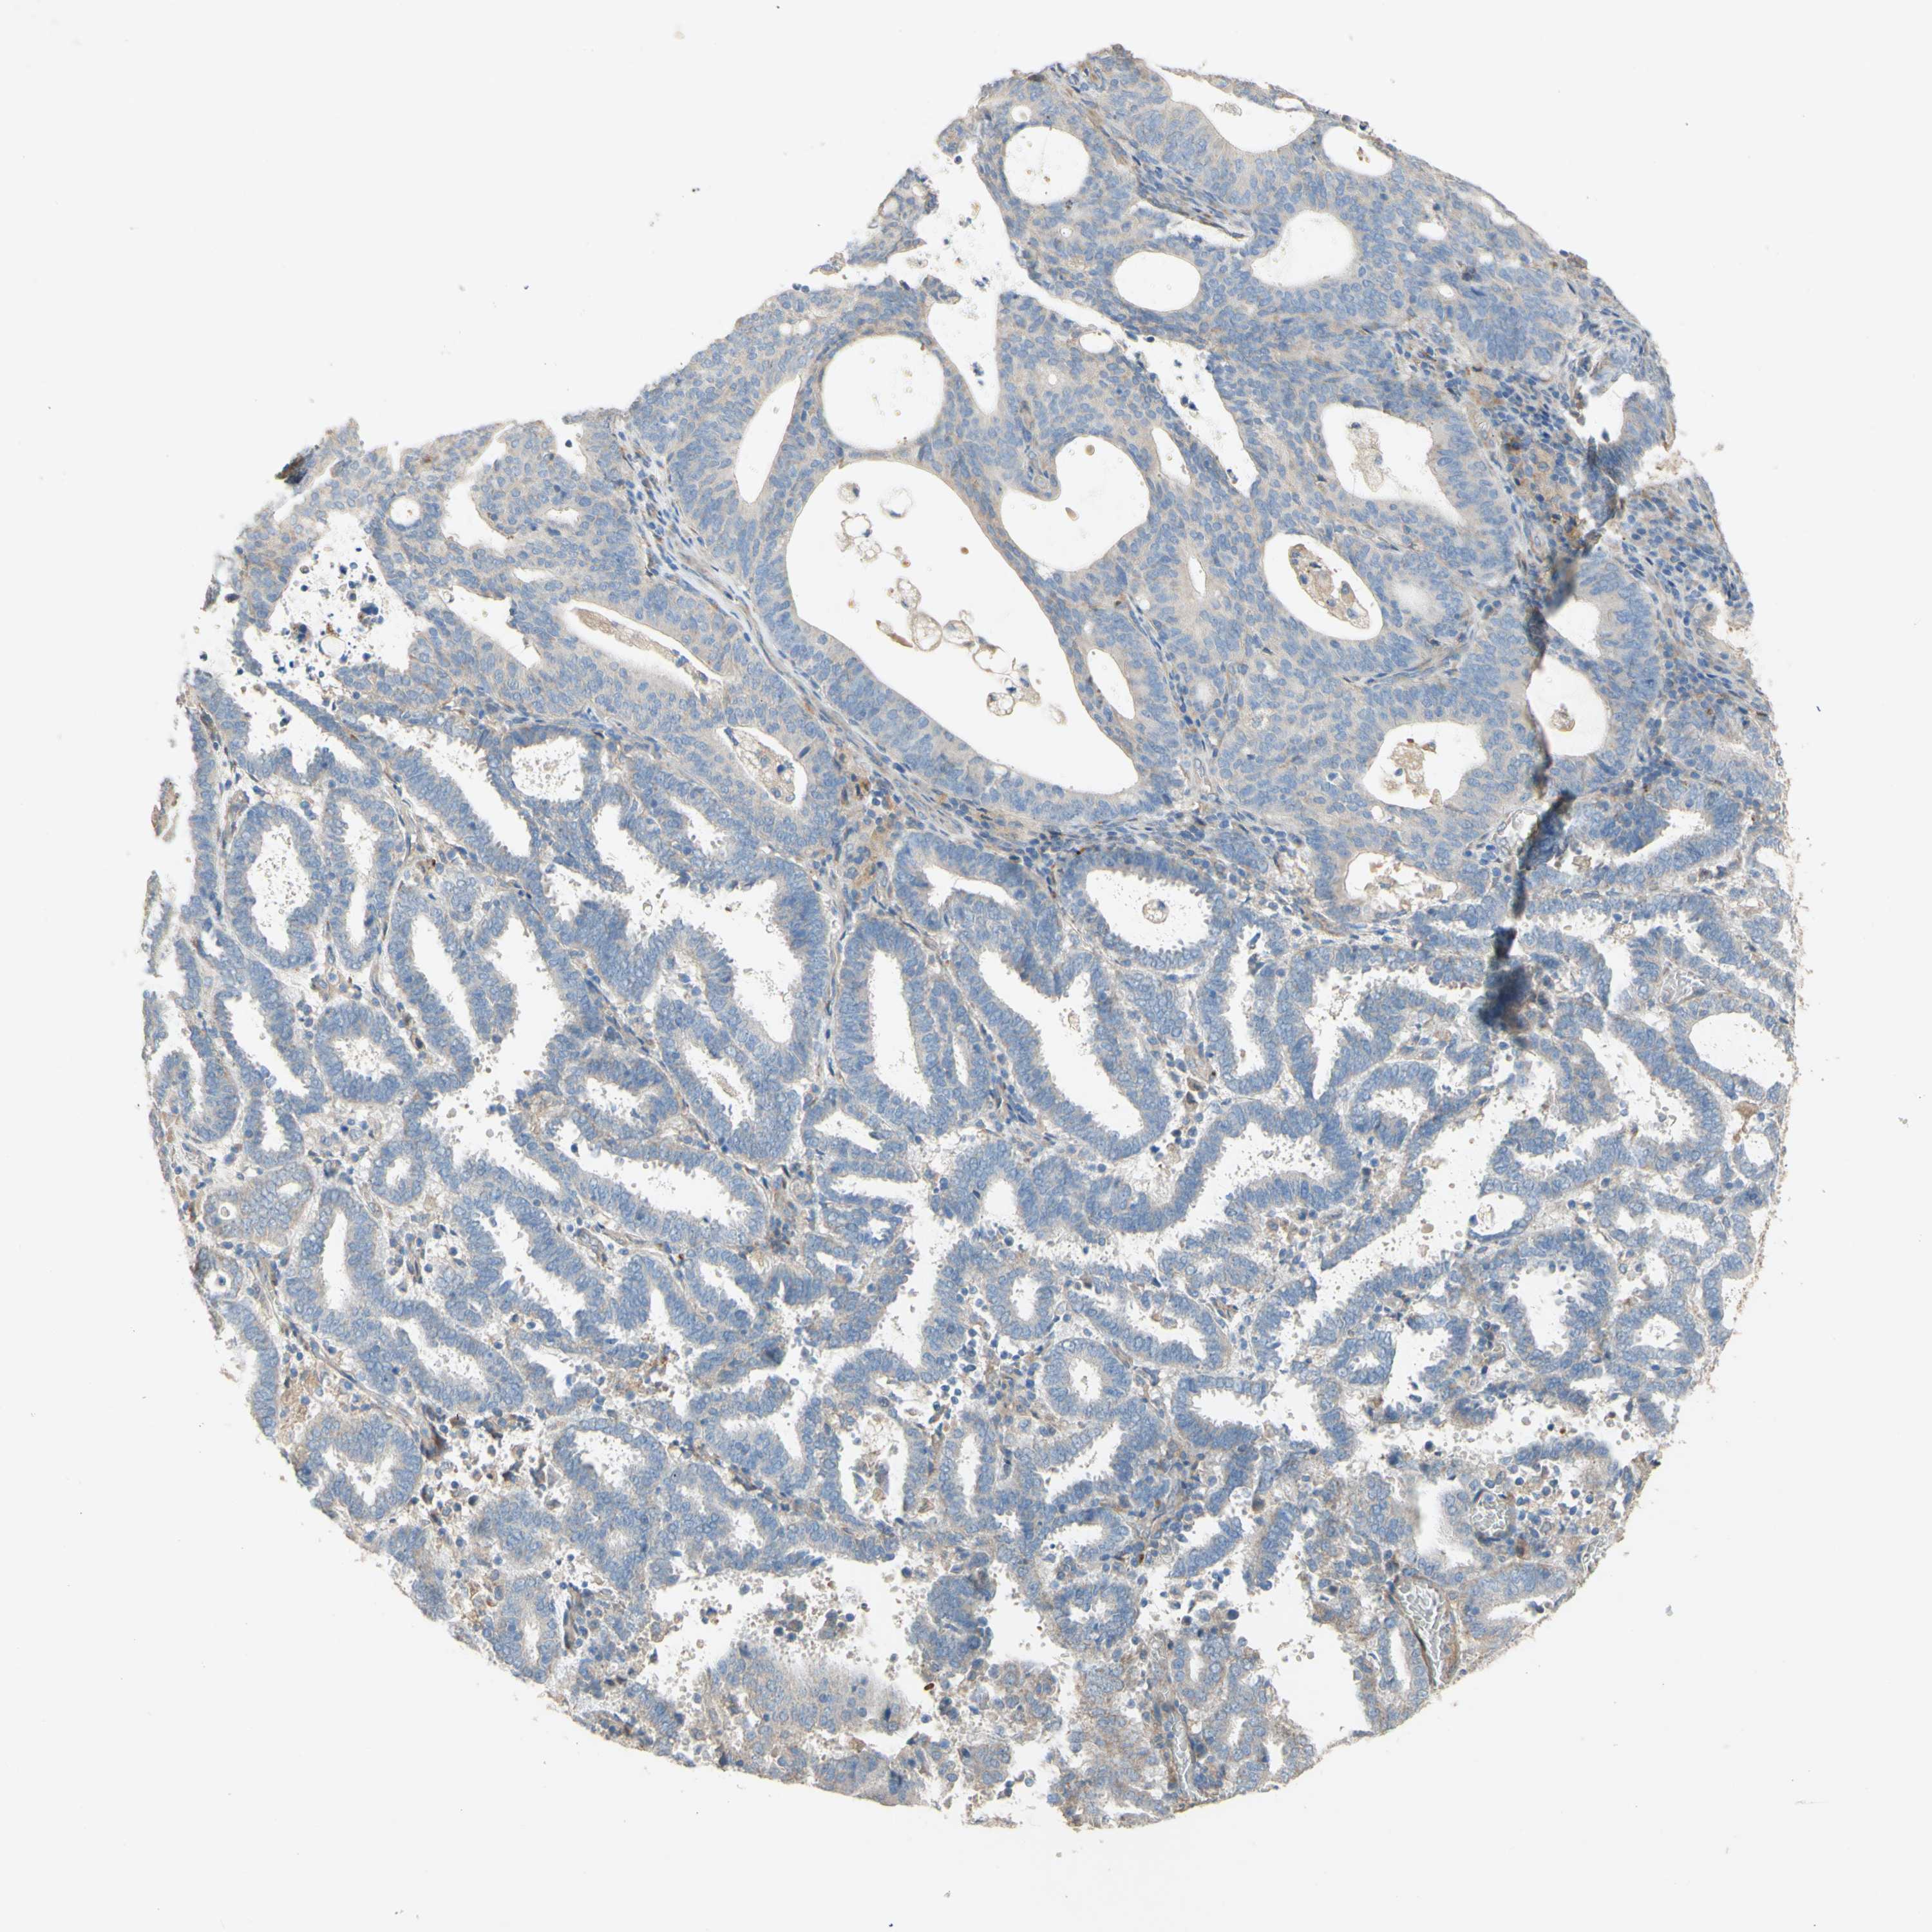

ENDOMETRIAL CANCER - Protein expressioni

A mouse-over function shows sample information and annotation data. Click on an image to view it in a full screen mode. Samples can be filtered based on level of antibody staining by selecting one or several of the following categories: high, medium, low and not detected. The assay and annotation is described here.

Note that samples used for immunohistochemistry by the Human Protein Atlas do not correspond to samples in the TCGA dataset.

Antibody stainingi

Antibody staining in the annotated cell types in the current human tissue is reported as not detected, low, medium, or high, based on conventional immunohistochemistry profiling in selected tissues. This score is based on the combination of the staining intensity and fraction of stained cells.

Each image is clickable and will lead to virtual microscopy that enables deeper exploration of all samples and also displays staining intensity scores, fraction scores and subcellular localization as well as patient and tissue information for each sample.

Antibody HPA011868

Antibody CAB024949

Staining

High

Medium

Low

Not detected

Intensity

Strong

Moderate

Weak

Negative

Quantity

>75%

75%-25%

<25%

None

Location

Nuclear

Cytoplasmic/membranous

Cytoplasmic/membranous,nuclear

Adenocarcinoma, NOS

Adenocarcinoma, metastatic, NOS